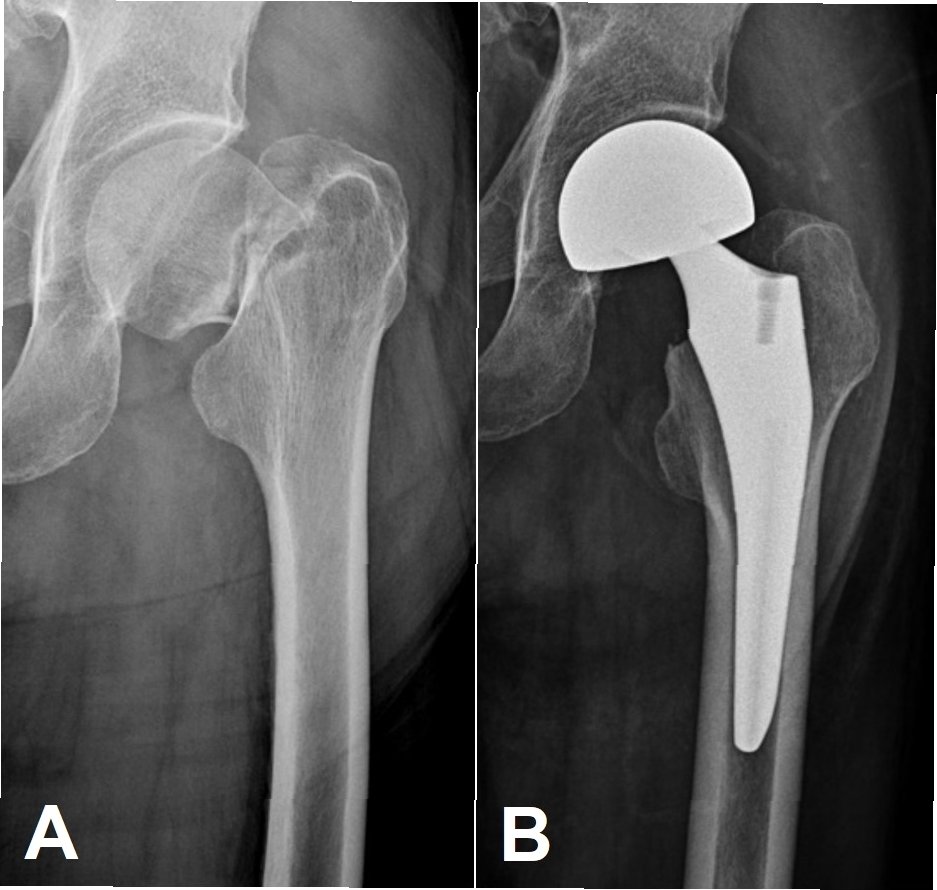

고관절 골절의 치료는 골절의 유형, 환자의 건강 상태, 연령 등을 고려하여 결정됩니다. 일반적으로 수술적 치료와 비수술적 치료가 있습니다. 수술적 치료는 골절 부위를 고정하기 위해 금속 내고정술(핀, 나사, 플레이트 등) 또는 인공관절 치환술을 시행합니다. 비수술적 치료는 골절 부위를 고정하고, 통증을 조절하며, 합병증을 예방하는 보존적 치료를 시행합니다. 수술 여부는 골절의 위치와 심각성, 환자의 전반적인 건강 상태에 따라 달라집니다. 수술 후에는 재활 치료를 통해 근력 강화, 관절 운동 범위 회복, 보행 능력 향상을 목표로 합니다. 재활 치료는 성공적인 회복을 위해 매우 중요한 과정이며, 전문적인 의료진의 지도하에 꾸준히 수행해야 합니다. 환자는 재활 치료를 통해 이전의 건강한 삶으로 돌아갈 수 있도록 노력해야 합니다.